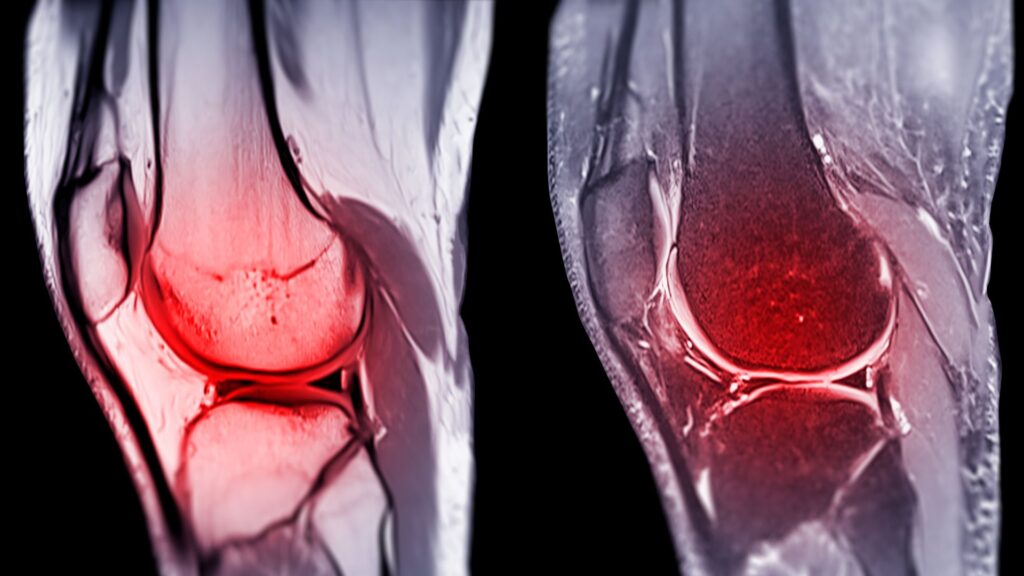

What Is an ACL Injury?

The anterior cruciate ligament (ACL) is one of the key stabilisers in your knee. It’s commonly injured during sports that involve pivoting, jumping, or sudden stops—but ACL tears can also happen during everyday activities like twisting or awkward landings.